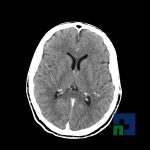

- Accidentelor vasculare cerebrale ischemice sau hemoragice

- Tumorilor cerebrale

- Evaluarea deplasării liniei mediane

- Diagnosticul edemului cerebral, a contuziei cerebrale, a leziunilor axonale difuze edematoase/hemoragice, a dilacerării cerebrale, a hematomului intraparenchimatos posttraumatic, a hematoamelor subdurale/extradurale (acute, subacute, cronice), a hemoragiei intraventriculare, a hemoragiei subarahnoidiene